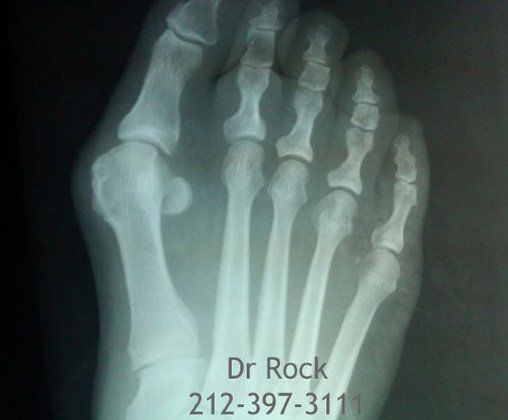

Take a look at our x-ray pictures of our recent footwork and see how your feet can benefit.

for more X-ray photos.